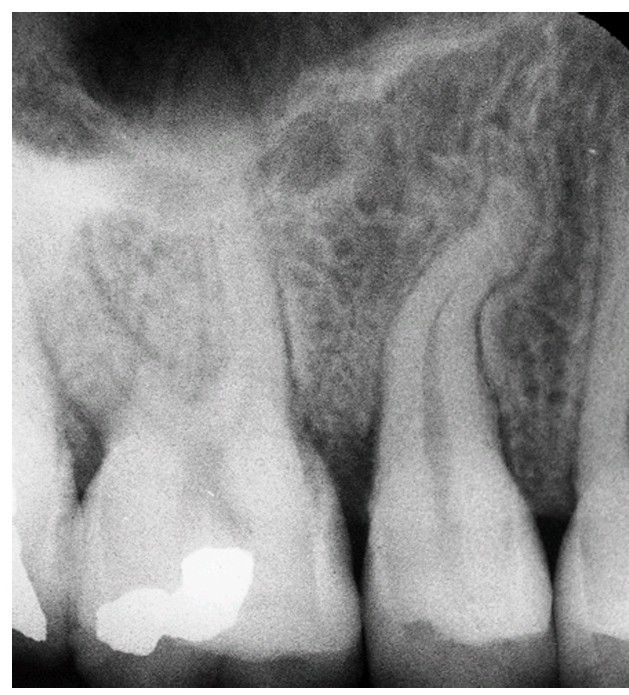

Dilaceration

Severe dilaceration of roots may result in fracture of the root unless surgical extraction is performed.